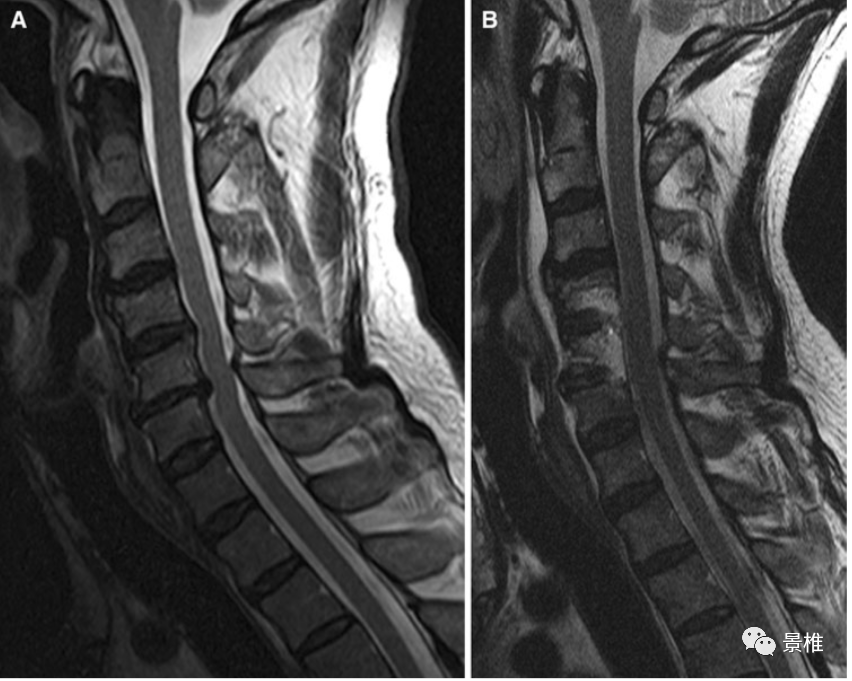

脊髓型颈椎病的诊治

入院后查颈椎mri示:椎间盘膨出,约平颈6以下颈胸髓内异常,考虑中央导